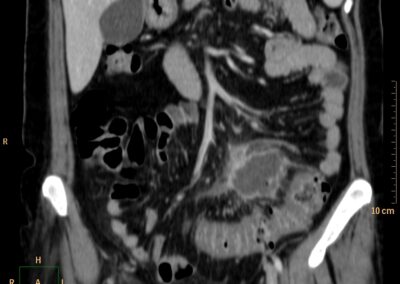

ΕΚΚΟΛΠΩΜΑΤΑ ΠΑΧΕΟΣ ΕΝΤΕΡΟΥ Posted by ΙΠΠΟΚΡΑΤΕΙΟ ΙΩΑΝΝΙΝΩΝ | Dec 16, 2020 | ΠΕΠΤΙΚΟ | 0 ΚΛΙΝΙΚΑ ΣΤΟΙΧΕΙΑ – ΙΣΤΟΡΙΚΟ υποτροπιάζοντες επαναλαμβανόμενοι πυρετοί κυρίως απογευματινές ώρες ΕΡΓΑΣΤΗΡΙΑΚΟΣ ΕΛΕΓΧΟΣ ΑΠΕΙΚΟΝΙΣΤΙΚΟΣ ΕΛΕΓΧΟΣ διακρίνονται τα αποστήματα στην ελάσσονα πύελο, καθώς και εκκολπώματα με εικόνα πάχυνσης του τοιχώματος του σιγμοειδούς ΣΥΖΗΤΗΣΗ